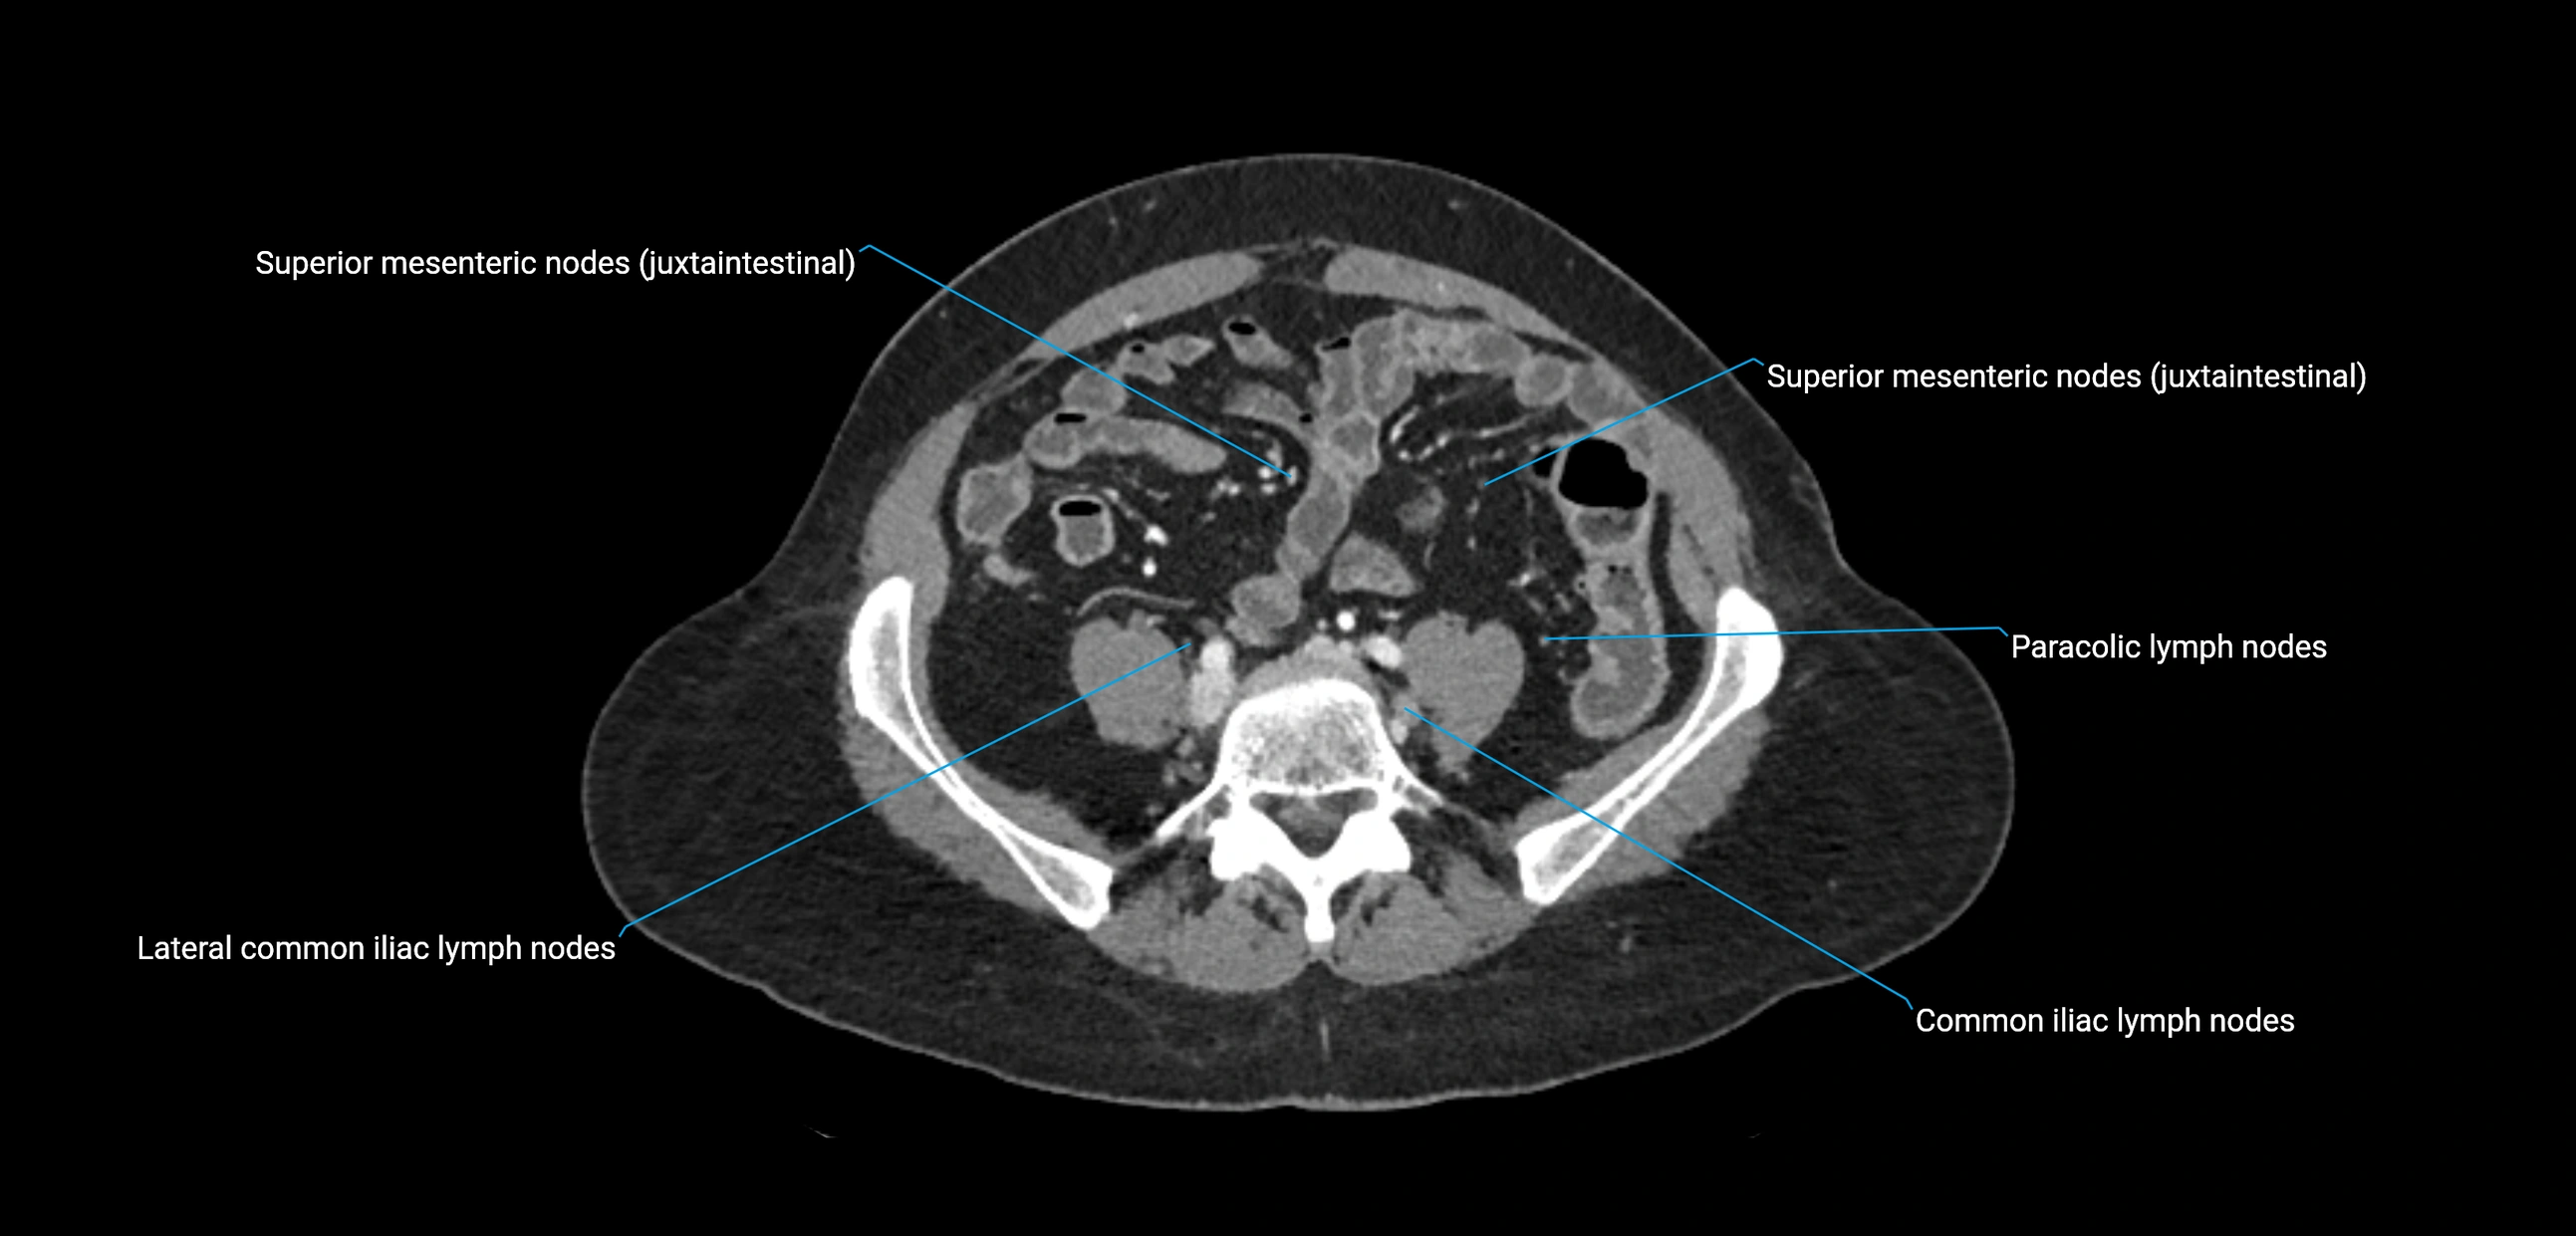

CT Appearance

CT Pre-Contrast:

• Nodes appear as soft-tissue density nodules adjacent to the aorta and IVC

• Calcification may be seen in chronic infections (e.g., tuberculosis)

CT Post-Contrast:

• Normal nodes enhance homogeneously

• Malignant nodes may show heterogeneous enhancement, central necrosis, or conglomerate formation

• Size >1 cm short axis is suspicious, though morphology and distribution are equally important